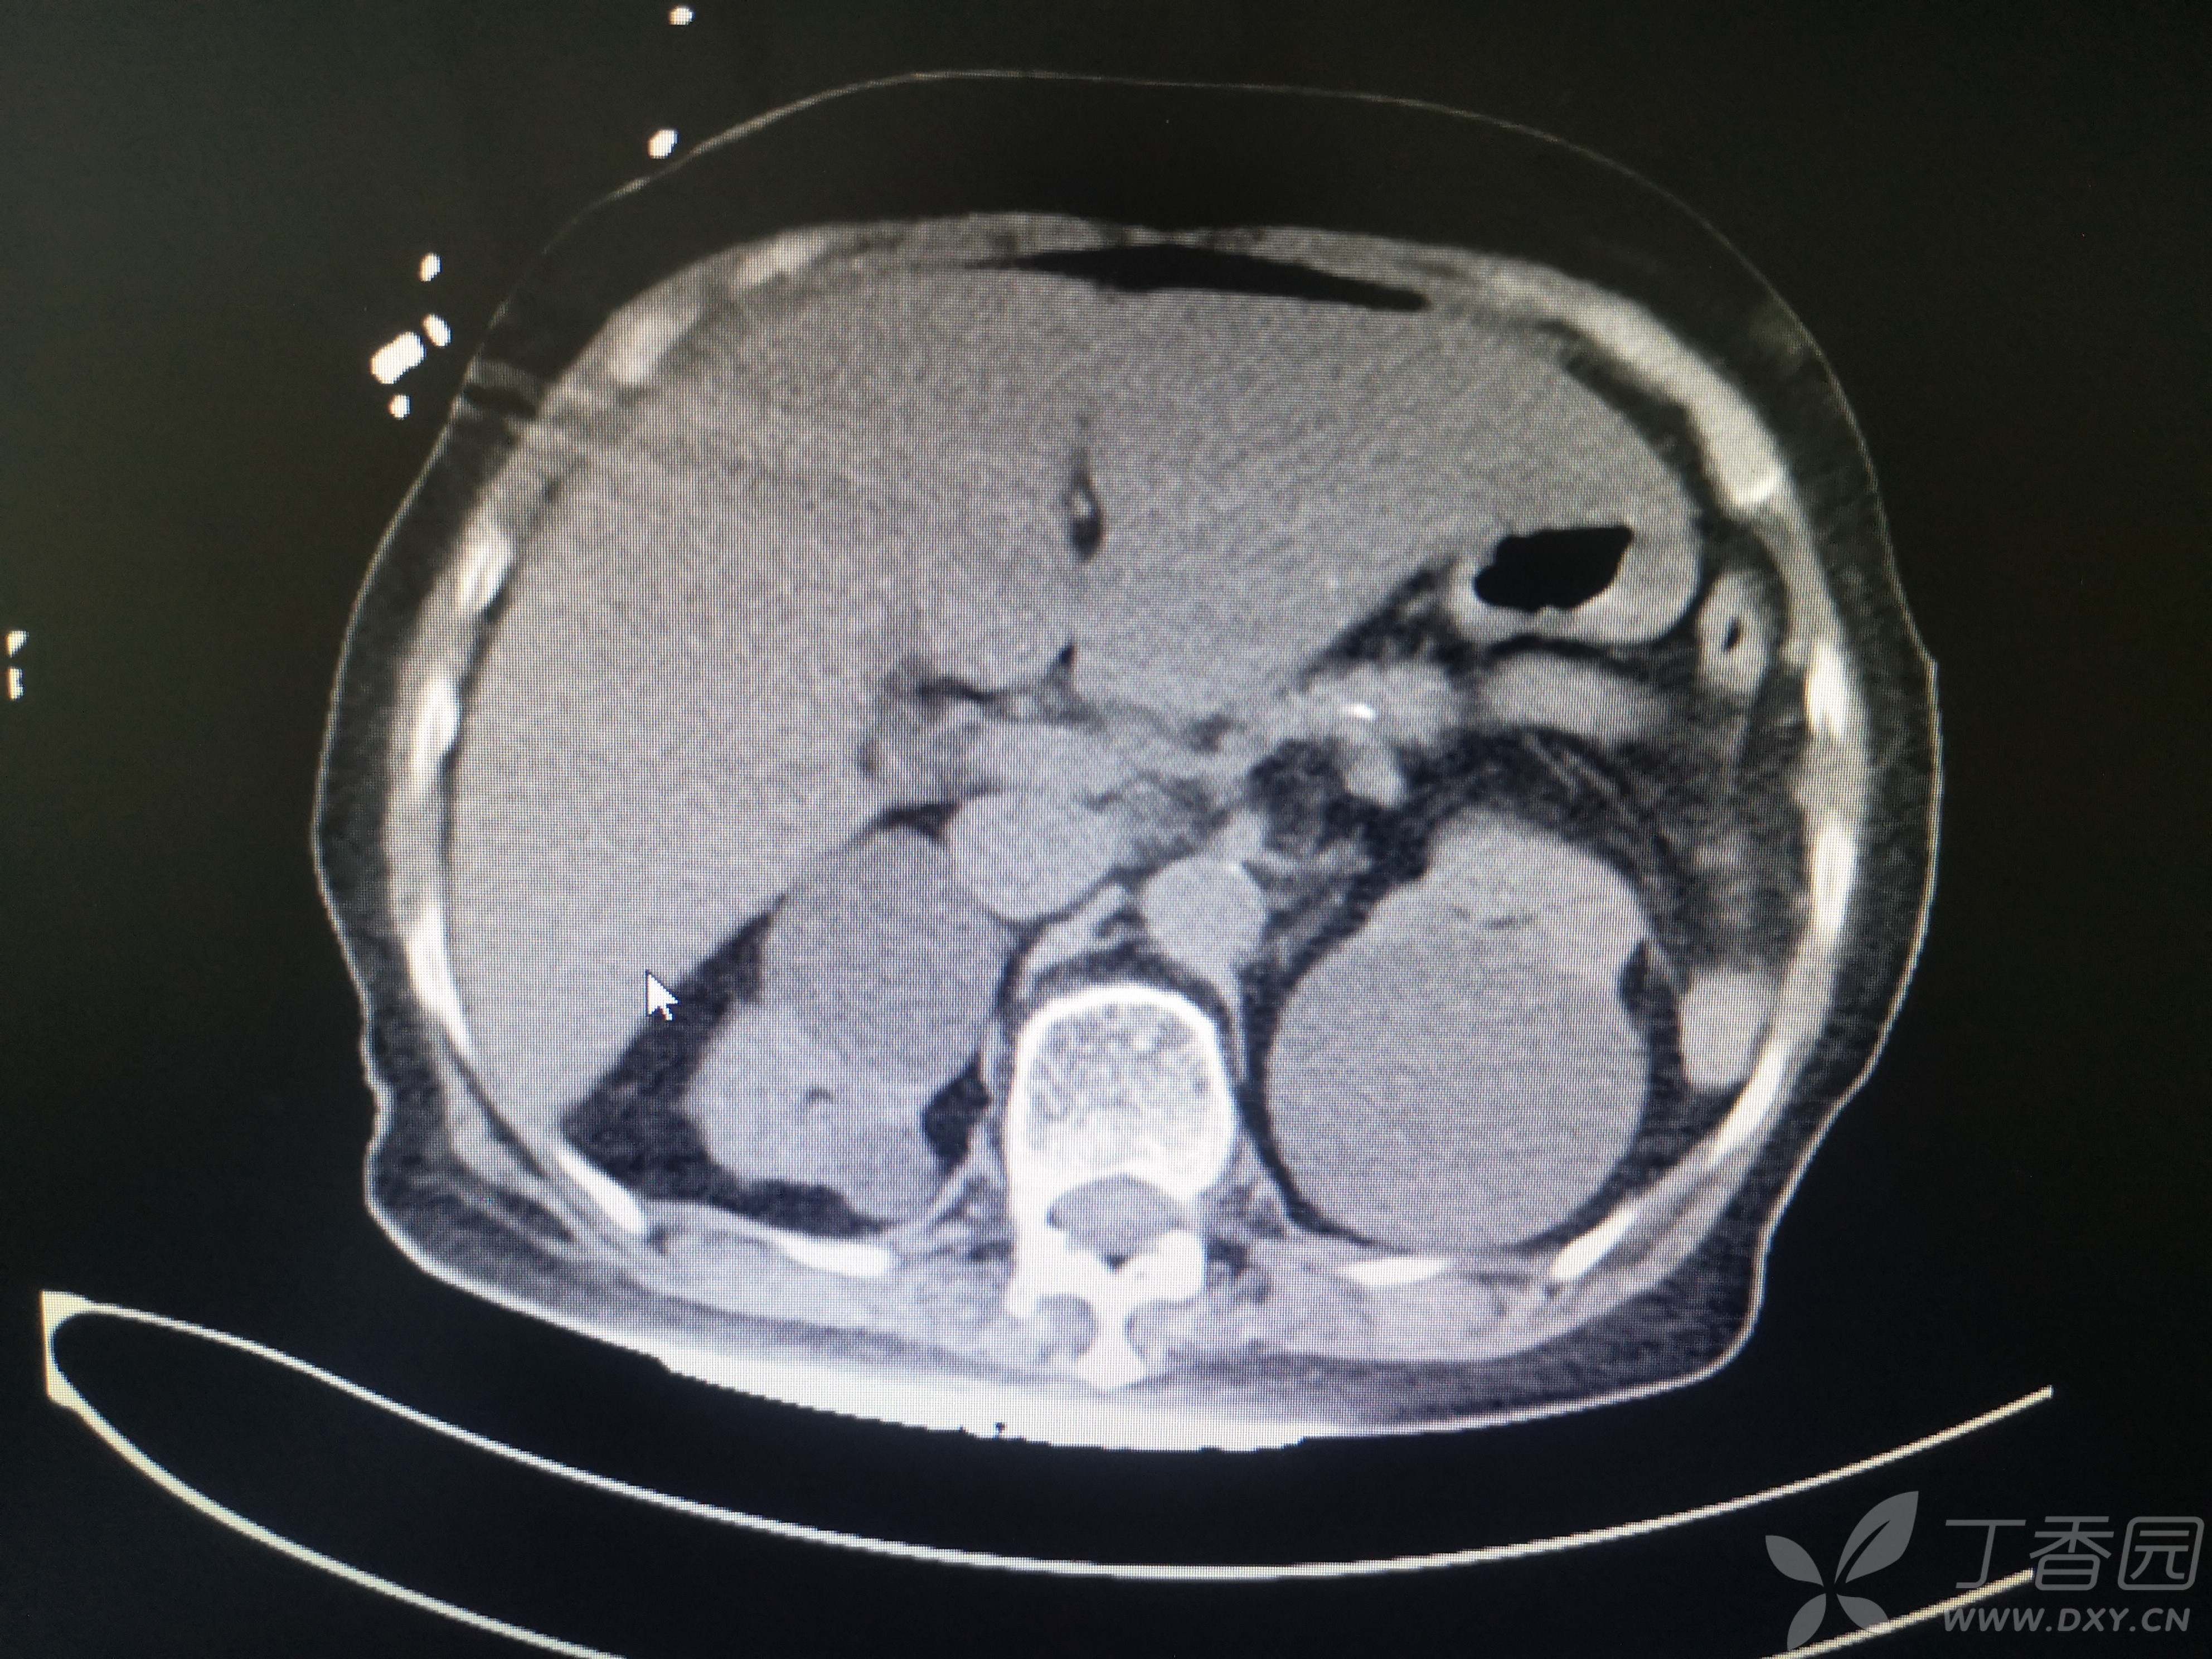

11小时前无明显诱因出现右腹部疼痛,伴恶心、呕吐,呕吐物清稀黏液,急至我院就诊,患者在家属搀扶下步入急诊室,神志清,言语费力,呼吸浅快,口唇、手足皮肤青紫,心电图示快速房颤,血压低至68/48mmHg,脉氧测不出,动脉血气分析PH 7.1,PCO2 13.6mmHg,PO2 135mmHg,Lac15.1mmol/L,HCO3 4.1mmol/L,K 6.11mmol/L。CT、血常规、血凝、生化等结果见图 。

患者CT图像如下

完善CT检查以后收入重症医学科治疗。